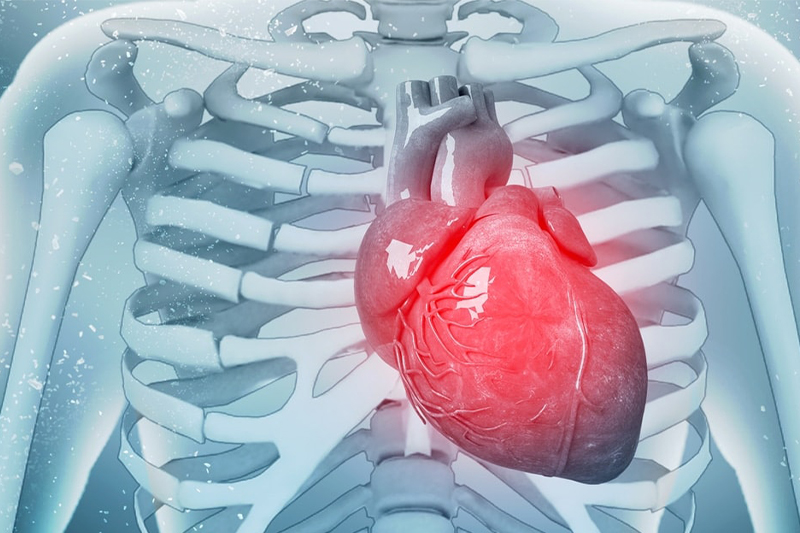

تُعرف النوبة القلبية باسم احتشاء عضلة القلب، وهي حالة طارئة تتطلب علاجا وشيكا. وحتى لو نجا الشخص من نوبة قلبية، فإن نقص الدم في القلب يمكن أن يضر عضلة القلب بشكل خطير. ويمكن أن تؤثر عدة عوامل على خطر تعرض الشخص لأزمة قلبية. وبالإضافة إلى عوامل نمط الحياة، يمكن أن يؤثر وجود حالات أخرى مثل […]readmore